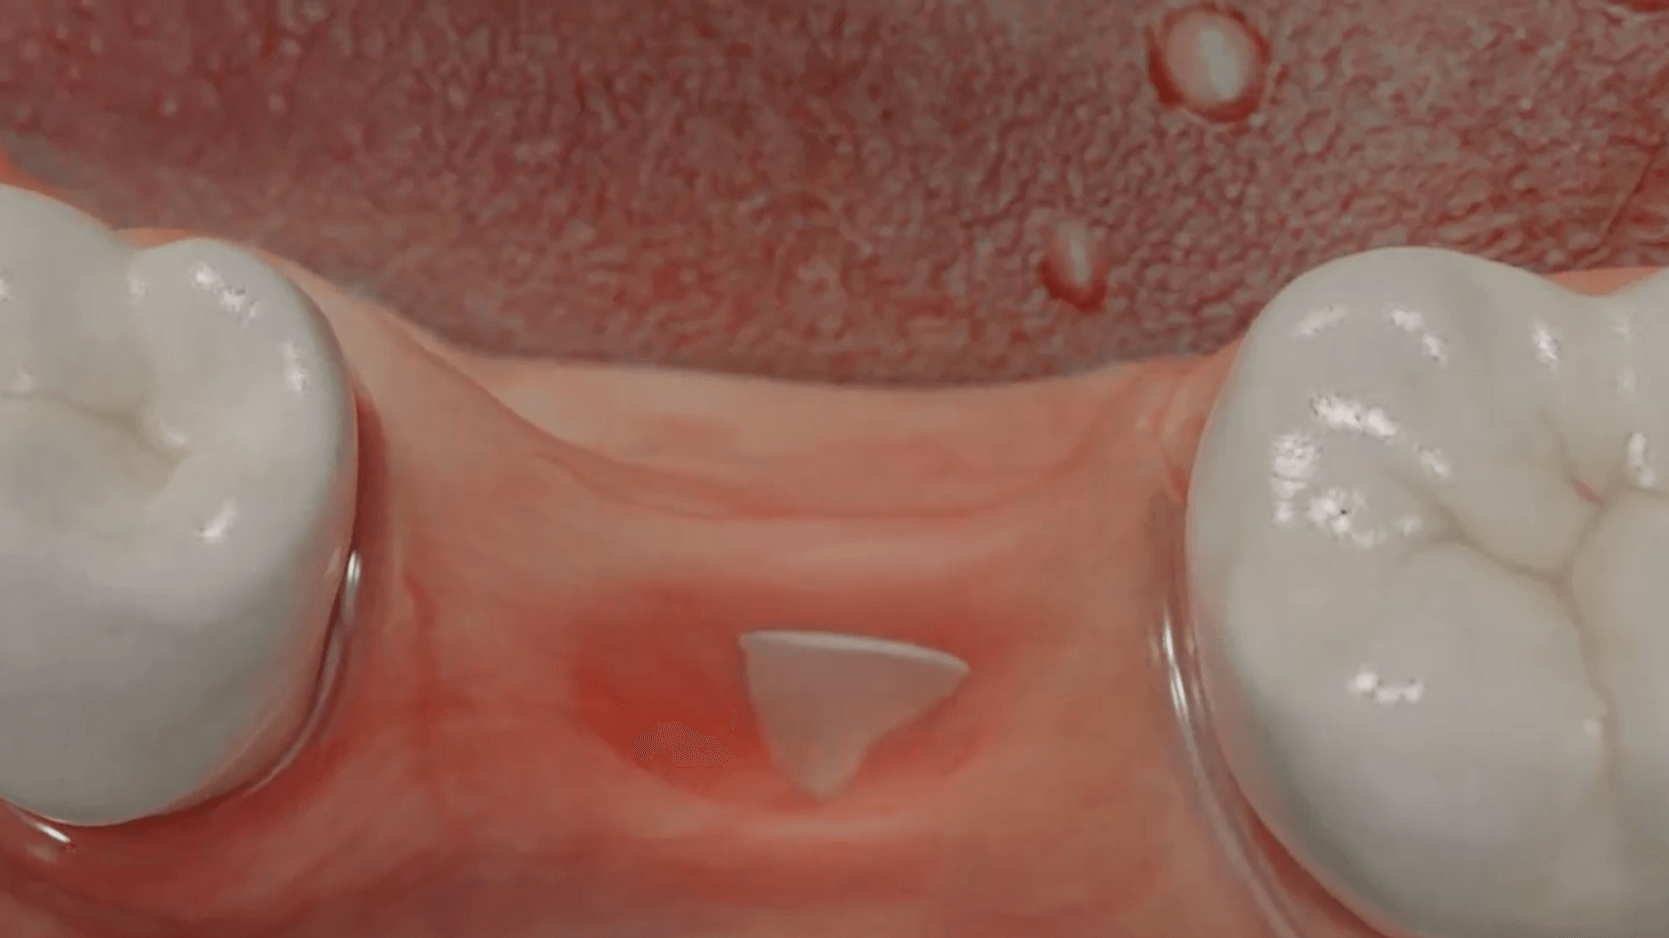

Durch den Verlust des Zahnes wandelt sich der Kieferknochen um. Nach der oberflächlichen Heilung wird das knöcherne Zahnfach vom Körper rasch abgebaut. Knochen ist für den Körper ein "teures" Gewebe, und ohne die funktionelle Kaubelastung durch einen Zahn gibt es für den Körper keinen Grund mehr, das knöcherne Zahnfach zu erhalten. Allein im ersten Jahr nach der Zahnentfernung gehen 50% des umgebenden Knochens verloren! Das ist insbesondere dann von Nachteil, wenn geplant ist, später ein Implantat für den Ersatz des Zahnes zu setzen. Ohne kiefererhaltende Maßnahmen reicht oftmals der nach der Heilung verbliebene Knochen nicht mehr aus, ein hinreichend großes Implantat einzusetzen bzw. dieses auch ideal zu positionieren.

Aus diesem Grund werden seit vielen Jahren

Knochenersatzmaterialien aus tierischem, pflanzlichen oder mineralischen Ursprung verwendet, um die Schrumpfung des Kieferknochens aufzuhalten und dadurch die ursprünglichen Dimensionen zu bewahren.